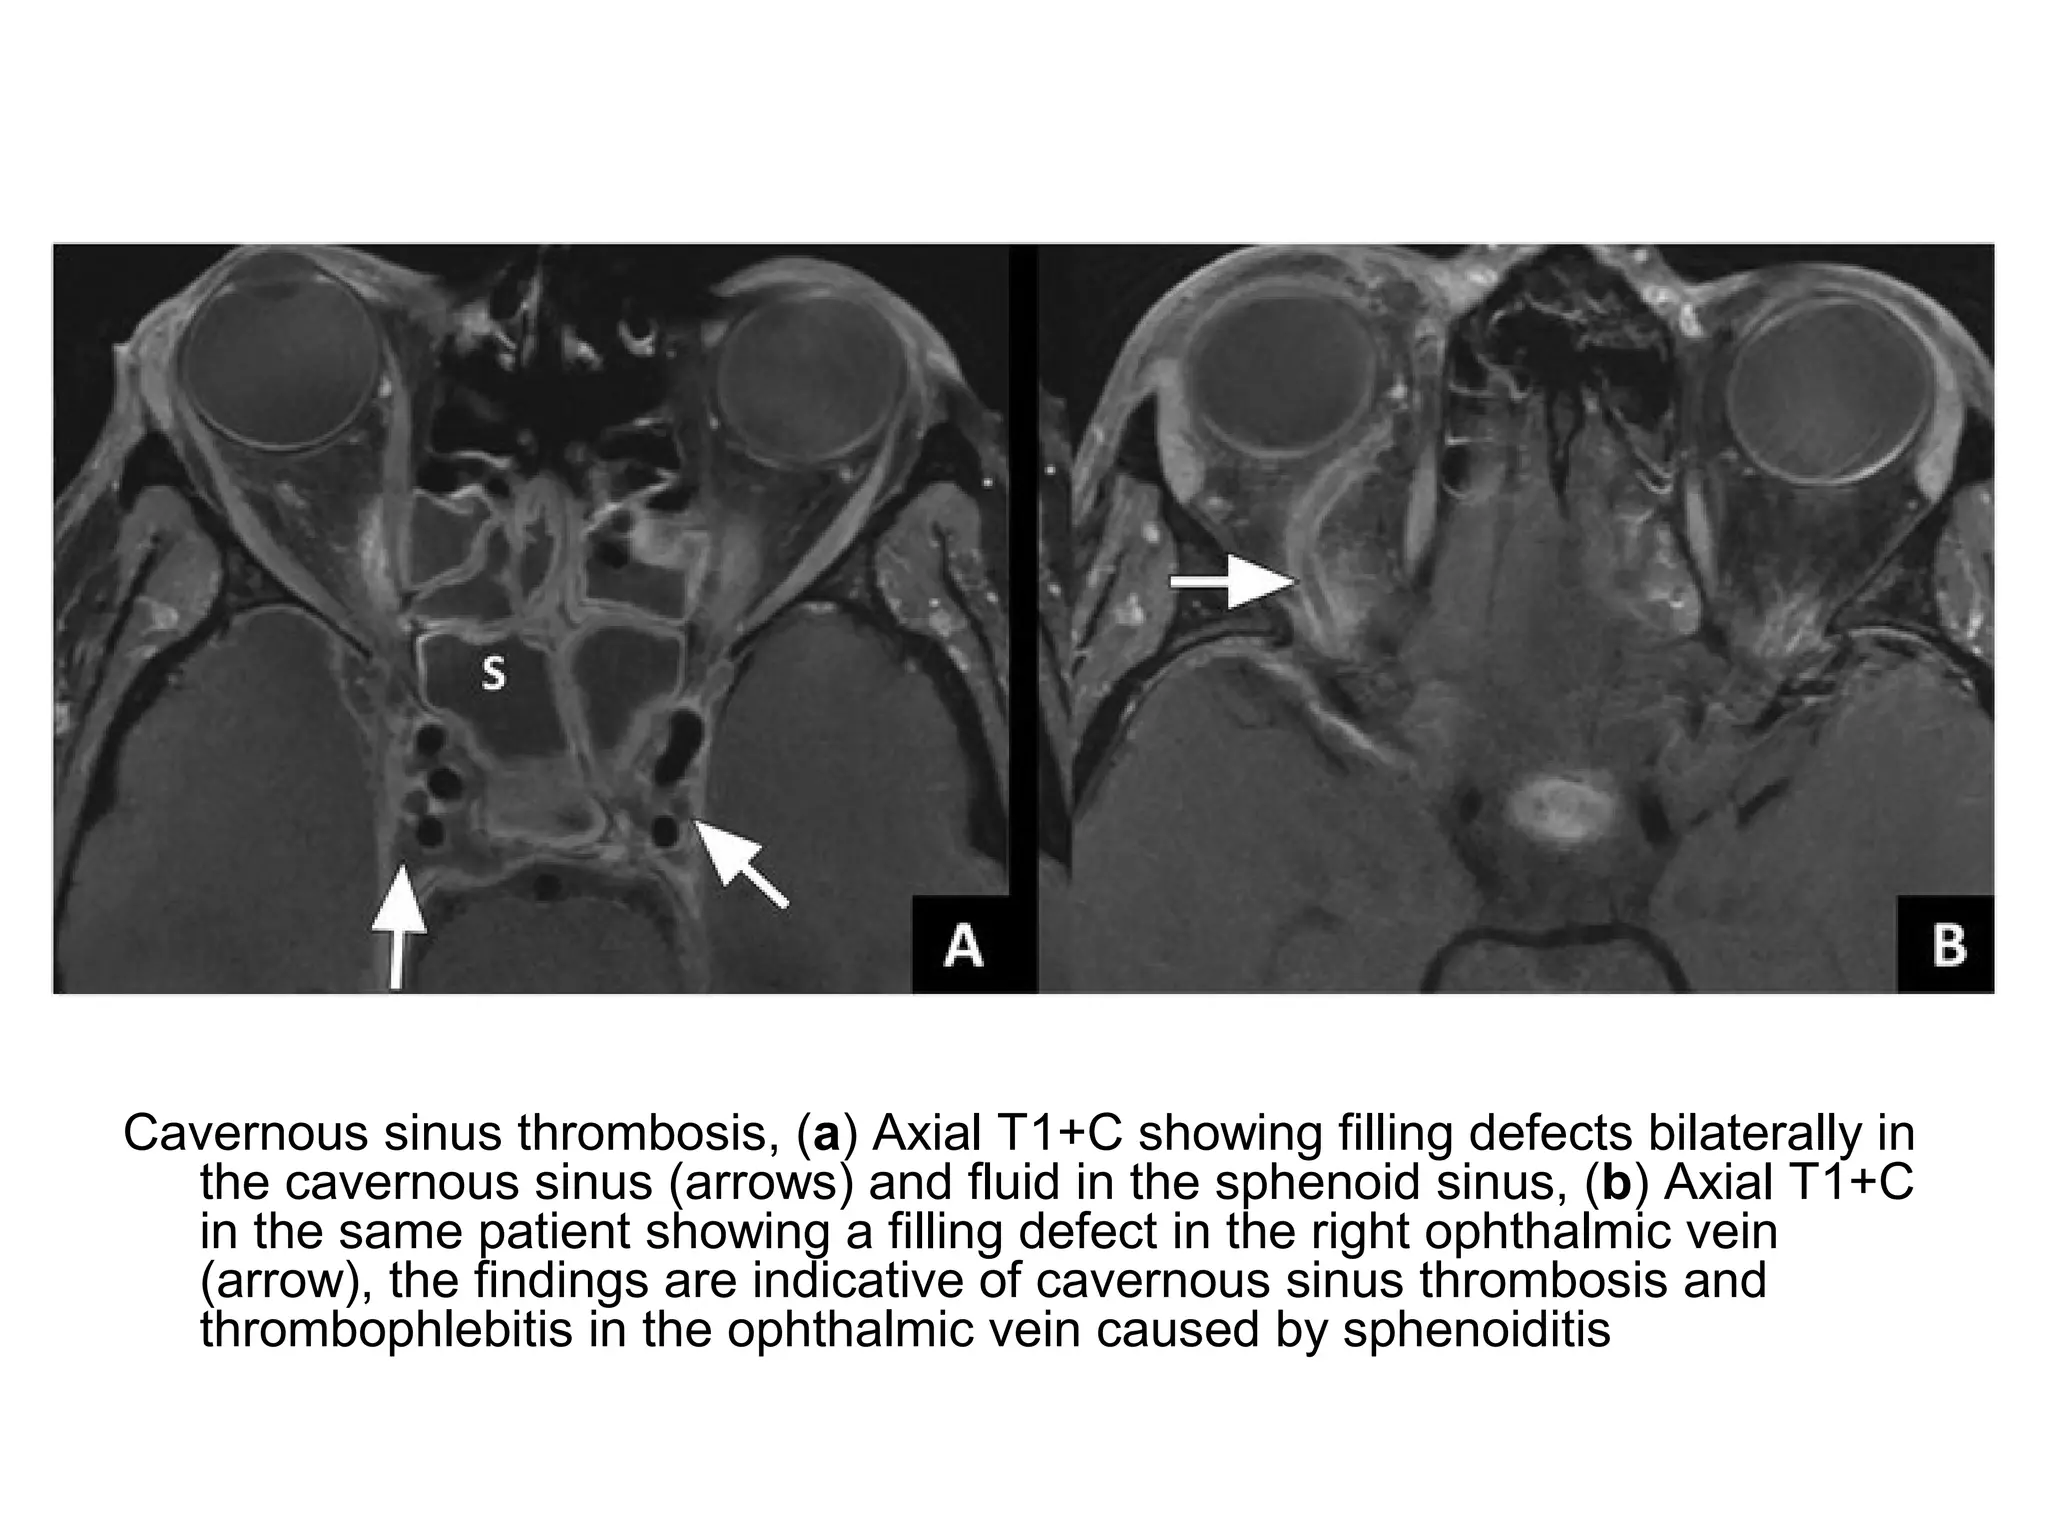

Cavernous sinus thrombosis, (a) Axial T1+C showing filling defects bilaterally in

the cavernous sinus (arrows) and fluid in the sphenoid sinus, (b) Axial T1+C

in the same patient showing a filling defect in the right ophthalmic vein

(arrow), the findings are indicative of cavernous sinus thrombosis and

thrombophlebitis in the ophthalmic vein caused by sphenoiditis